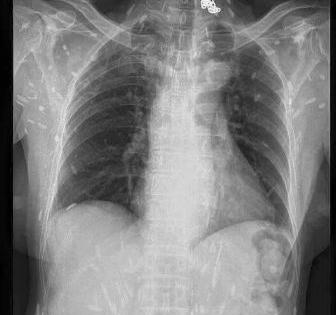

Mấy ngày gần đây, cộng đồng mạng chia sẻ các bức ảnh chụp X-quang rất khủng khiếp của một bệnh nhân nhiễm sán. Theo đó, trên các bức ảnh X-quang là la liệt các xác sán xơ mít có đầu vôi hóa hình như hạt gạo. Theo các bác sĩ, nguyên nhân bị nhiễm sán là do ăn phải thức ăn sống như rau sống, tiết canh, gỏi cá… có nhiễm trứng, ấu trùng sán.